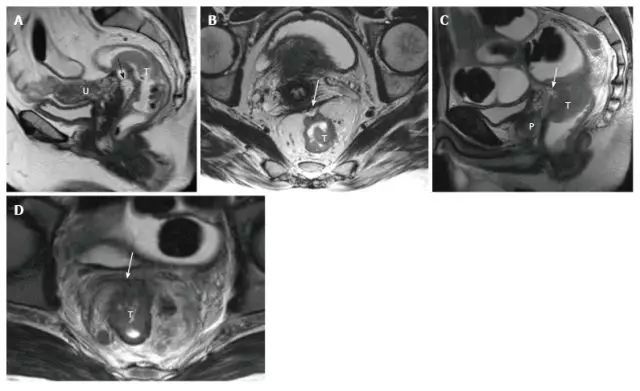

腹膜反折覆盖上段直肠前壁,矢状位在男性精囊腺上极和女性宫颈角上方。腹膜侵袭的评估在分期中非常重要,因为直肠肿瘤在腹膜受侵的情况下分期为 T4a。

图片

图 5. 女性(A 和 B)和男性(C 和 D)腹膜受侵 T4a 直肠肿瘤患者。在矢状位 T2 加权图像上,腹膜是肿瘤前面的低信号线性结构(A,C 中的箭头)。在轴位 T2 加权图像上,腹膜具有 V 形并且附着在直肠癌的前面(B 和 D 中的箭头)。T:肿瘤;U:子宫;P:前列腺。